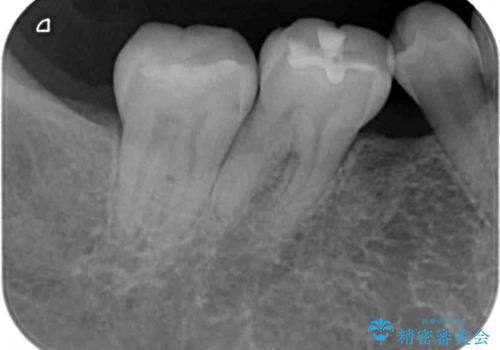

- 上下前歯のデコボコと奥歯の欠損を気にして来院された患者様です。

右下の欠損分は奥歯が倒れ込んでスペースがなくなっていたため、矯正治療により本来の位置に歯を移動させ、オールセラミックブリッジによる欠損補綴治療を行うこととしました。

右下は移動量が多いため、十分な移動が達成されない場合はワイヤー装置を使用する予定としておりましたが、しっかりとマウスピースを装着してくださったため、前歯とともに十分に歯を動かすことができました。